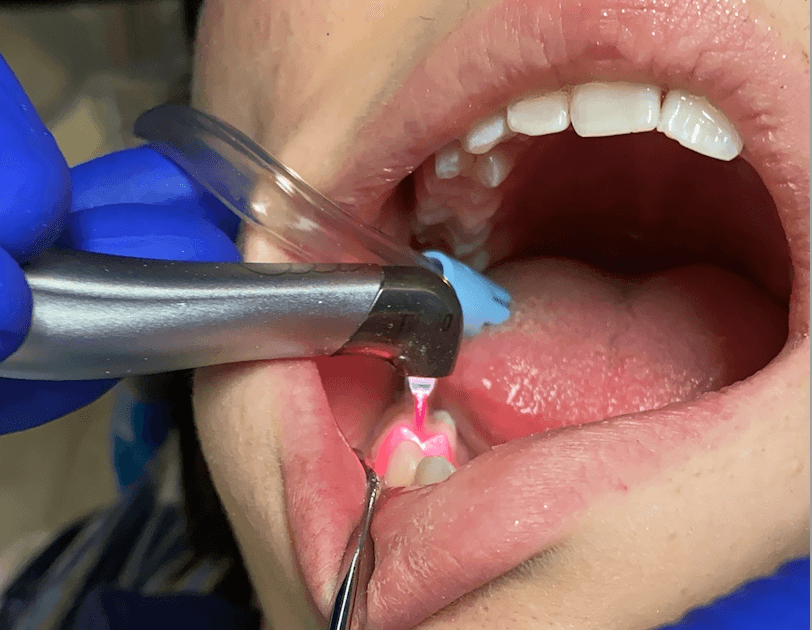

بیحسی موضعی و آمادهسازی ناحیه: برای راحتی کامل بیمار.

پاکسازی مکانیکی (SRP) و دبریدمان: پایهی درمان پریودنتال.

کار با لیزر بر اساس پروتکل: هدایت فیبر/هندپیس بهصورت کنترلشده در پاکتها، کاهش خونریزی و کاهش بار میکروبی.

ایجاد شرایط ترمیمی بهتر: بافتهای بیمار برداشته/کوآگوله میشود تا شرایط چسبندگی بهتر فراهم گردد.

aPDT (فوتودینامیک ضدمیکروبی): رنگ حساسگر + نور → تولید رادیکالهای اکسیژن برای تخریب باکتریها؛ بهعنوان مکمل SRP نتایج امیدوارکنندهای در پاکتهای مزمن نشان داده، و در برخی مرورها از آنتیبیوتیک سیستمیک هم جلو زده است؛ البته انتخاب مورد به عهده پزشک است.